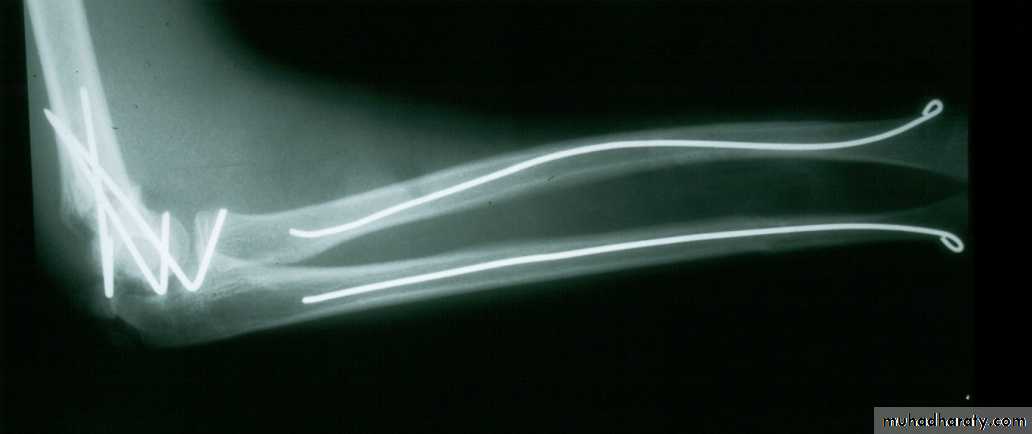

How about retrograde IM Fixation??

Must visualize the medial epicondyle

8 y.o. rolled over on an ATV

with mild closed head injuryClinical appearance

Only N-V deficit:

Anterior interosseous n. function weak

Radial A.

FCR Musc.Imaging Studies

How are we going to stabilize this boy’s fracture?

This is probably one of the few indication to use

Antegrade Flexible I M NailsOur Patient P.O.

Probably acts more

as an internal splintSix months post-operative